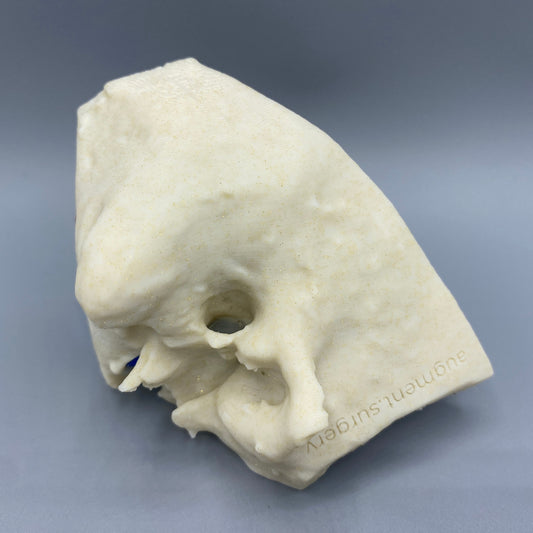

Plant-based surgical simulators made in the U.S.A.

Dissect each one to learn human temporal bone anatomy, hearing and vestibular systems.

Customize anatomy, colors, quantities, and more by contacting michelle@augment.surgery